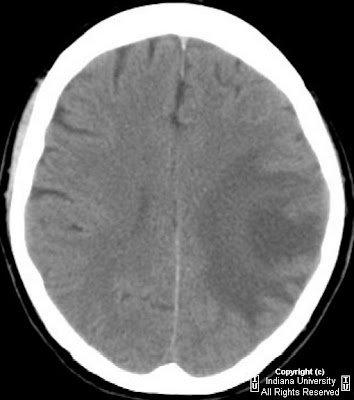

Glioblastoma Multiforme - University Of Missouri

Glioblastoma Multiforme. A . glioblastoma multiforme. is a malignant, primary brain tumor. It is the most common adult brain neoplasm, that has a rapid growth rate and complete surgical incision is impossible. ... Retrieve Document